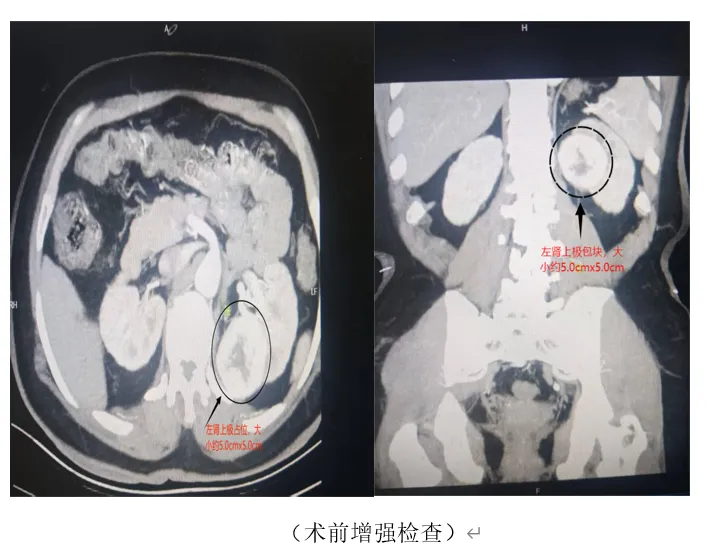

近日,62岁的王某因椎间盘突出症,经朋友介绍来到松桃苗族自治县民族中医院骨二科后,经科室团队为他行椎间孔镜微创手术,第二天能佩戴腰围下床走路,配合中(苗)医药治疗和口服助力康复,目前恢复良好,即将出院...